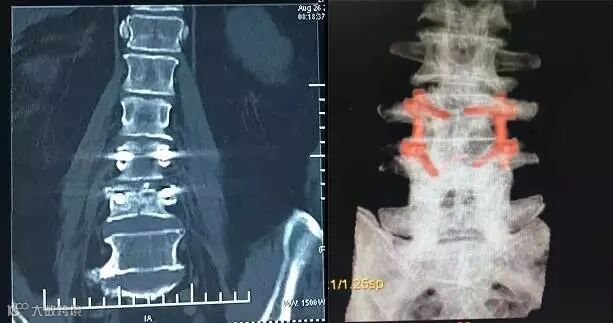

【术后X线】

【术后CT】